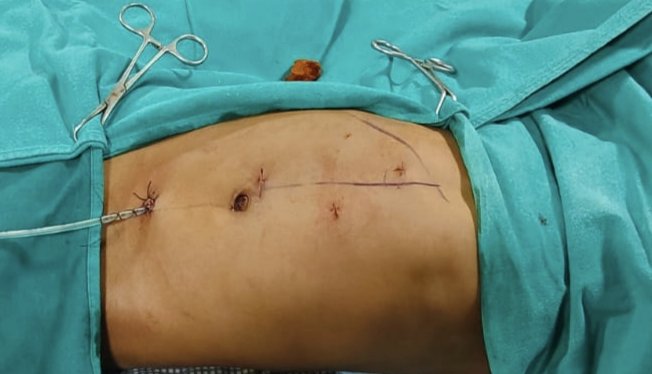

6-month hands-on training in: 🔹 RIRS

🔹 PCNL

🔹 Laparoscopy